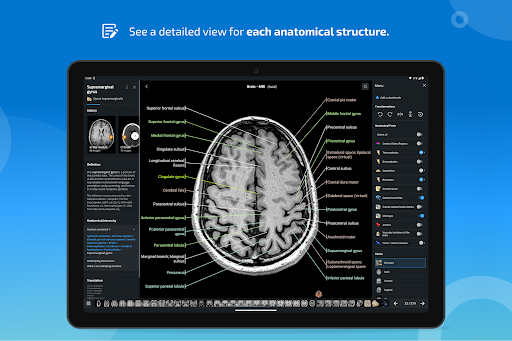

e-Anatomy memiliki lebih dari 26.000 gambar yang berisi serangkaian gambar dalam tampilan aksial, koronal, dan sagital serta radiografi, angiografi, gambar diseksi, bagan anatomi, dan ilustrasi. Semua gambar medis diberi label dengan cermat, lebih dari 967.000 label tersedia dalam 12 bahasa termasuk Terminologia Anatomica Latin.

- Ketuk label untuk menampilkan struktur anatomi

*Peningkatan tampilan detail bagian anatomi untuk memudahkan identifikasi dalam gambar modul saat ini dan modul lainnya.

tampilan detail istilah terkait struktur anatomi sekarang ditampilkan

-Dalam tampilan detail struktur anatomi , pin sekarang menunjukkan struktur terkait di semua gambar yang ada